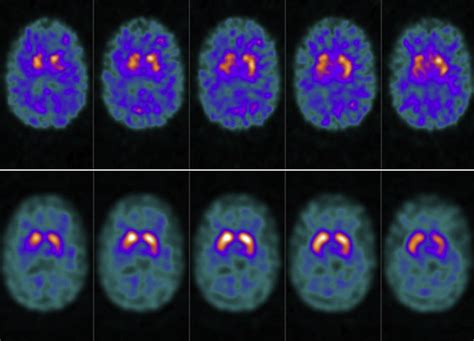

During the procedure, a small amount of a radioactive tracer is injected into the patient’s bloodstream. This tracer binds specifically to the dopamine transporters. Once the tracer has circulated, a specialized camera captures images that reveal how these transporters are distributed throughout the brain. A healthy scan shows a symmetric, comma-shaped appearance in the striatum, whereas a scan showing a reduction or distortion in these areas may indicate pathology.

The results of a Dat Scan are analyzed by a radiologist or nuclear medicine physician who assesses the density and distribution of the tracer. In patients with Parkinson’s disease, the imaging will typically show a significant decrease in the intensity of the signal in the striatum, often appearing as a loss of the "comma" shape.